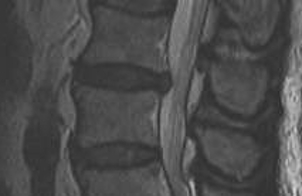

MRI

T2 Sagittal - myelogram

T1 Axial - see nerve root against white fat